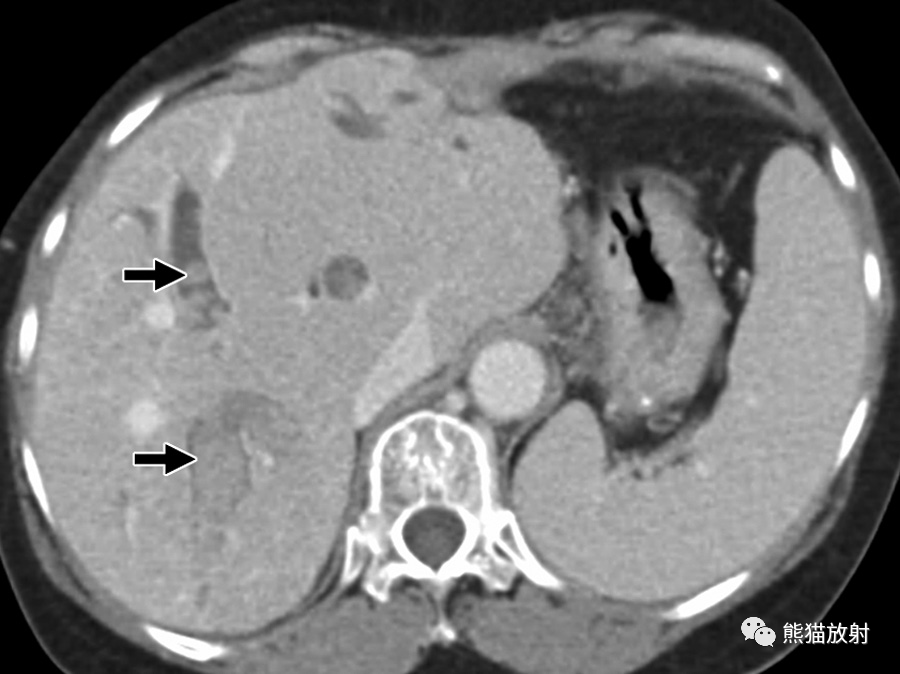

24岁男性,HIV感染患者,盗汗、发热,播散性结核感染。对比增强CT显示肝脏(黑箭)和脾(箭头)实质内多发微小低密度病变,腹膜后多发增大淋巴结(白箭)。

6岁男孩,肝巴尔通体病,被猫抓伤后发热3周。轴位增强CT图像显示多个低密度肝结节(箭)及门静脉周围增大淋巴结(箭头)。这些病变与转移瘤鉴别困难。然而,在无已知恶性肿瘤的免疫功能正常的年轻患者中观察到多发性肝脏病变应考虑到有肝巴尔通体病的可能。

巴尔通体病(猫抓病)是由巴尔通体引起的感染,该革兰氏阴性菌通过猫抓或咬伤引入人类宿主,最常影响儿童和年轻成人。猫抓或咬伤后1-3周开始出现症状,受伤部位近端出现疼痛性淋巴结肿大和发热。在无淋巴结肿大的情况下可发生内脏受累,表现为不明原因的发热。巴尔通体病的诊断可通过血清学试验、PCR试验或活检证实。播散性感染见于5%-10%的病例 。肝巴尔通体病的特征是多发性坏死性肉芽肿,范围为3-30mm,伴或不伴肝肿大。